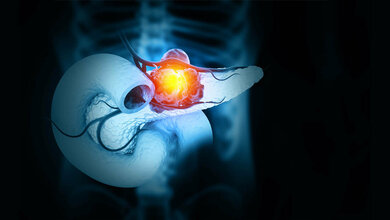

In der Krebsmedizin wird zudem für viele Menschen die Translation neuer Erkenntnisse in die Versorgung direkt sichtbar. So sind für einige Krebserkrankungen Immuntherapeutika in Deutschland bereits in der Routine angekommen.